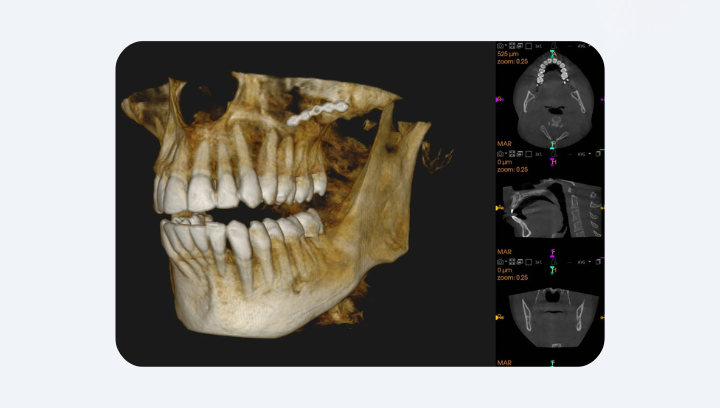

Компьютерная томография (CBCT — Cone Beam Computed Tomography) работает по совершенно иному принципу. Аппарат делает сотни узких срезов, вращаясь вокруг головы пациента, а компьютер объединяет их в полную 3D-модель челюсти. Врач может «прокрутить» её, разрезать в любом направлении, изменить масштаб и увидеть даже мельчайшие детали — корневые каналы, нервы, микротрещины, плотность кости. КТ рекомендована во всех случаях, когда 2D-снимок не даёт достаточной информации для клинического решения. И именно поэтому, когда врач говорит: «Нужно сделать КТ», — он не перестраховывается. Он просто хочет работать не наугад, а точно.

В результате врач получает полноценное 3D-изображение, которое можно рассматривать слой за слоем — в любой плоскости, в любом масштабе. Он может вращать модель, делать срезы по оси, изменять прозрачность, измерять расстояния с точностью до десятых миллиметра. Это не просто «снимок» — это цифровая копия челюсти пациента с анатомической точностью.

MARS (Metal Artifact Reduction) — программное снижение артефактов от металлических коронок, пломб и имплантов.